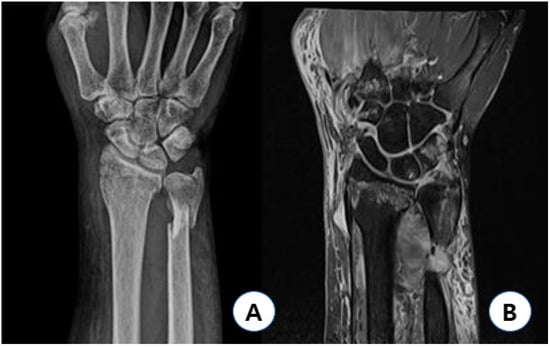

Radial avulsion injury (D1) was detected in only one case, which showed a volar angulated fracture and the greatest increase in radial-length distance (Figure 3). In this case, both distal radioulnar fractures occurred; however, there was greater displacement of the distal ulnar fracture fragment, which was shortened in length, and the distal radius was volar angulated. The patient was driving at the time of injury, with her wrist in a flexed position; as the car came to a sudden stop, she suffered a direct injury from the car handle with her wrist in a flexed position. In this case, considering DTM, the direct axial force that was applied while her wrist was in a state of ulnar flexion caused greater displacement of the distal ulnar fracture. Unlike Colle’s fracture mentioned above, ulnar-deviated and volar-angulating axial force decreases the tension on the palmar soft tissue of the TFCC and makes the detachment of sECU from the ulnar side more difficult, thereby transmitting the axial force to the radial avulsion of the TFCC.

Figure 3. Type 1D injury case. Sixty-three year-old female patient injured with her wrist flexed had AO/OTA type A2 fracture with 15′ volar angulation, showing 5 mm increased radial length gap (A), and had type 1D TFCC injury with relatively preserved peripheral and distal portion of TFCC (B). AO: arbeitsgemeinschaft fur osteosynthesfragen; OTA: orthopedic trauma association; and TFCC: triangular fibrocartilage complex.